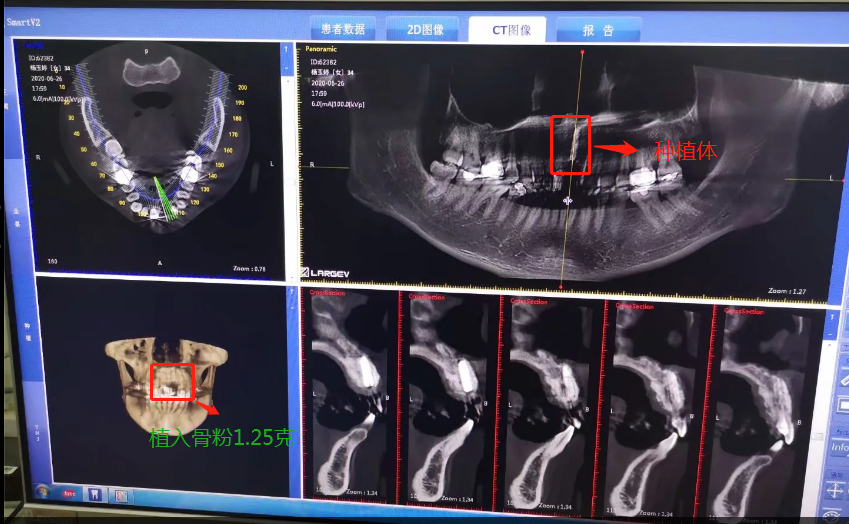

2020年6月26日,終于等到了,我要種植了牙根啦,我牙根弄了法國安卓建品牌的種植體,之前還去幾家口腔門診和烈士陵園的光華口腔也咨詢過和對(duì)比價(jià)格,瑞士ITI品牌太貴了(還有別的品牌M美國皓圣、韓國登騰、德國ICX、瑞典諾貝爾等),本來選美國皓圣,但我的是門牙,要選材質(zhì)比較好,考慮美觀問題,后選擇中等價(jià)位的安卓健。手術(shù)很快,而且傷口不是很大,我四天就康復(fù),做完當(dāng)下就可以說話,完全沒有阻礙。因?yàn)檠栏N進(jìn)去必須要等半年時(shí)間跟我骨頭長(zhǎng)在一起,因?yàn)槲耶?dāng)時(shí)做手術(shù)的時(shí)候種植入的骨粉還是軟的,還沒有變成硬骨頭。現(xiàn)在的階段是等待上基臺(tái),上完基臺(tái)半個(gè)月時(shí)間上牙冠。2020年12月26日上基臺(tái)。預(yù)計(jì)要2021年1月份可以全部完成種牙過程,期待著我?guī)涎例X的那一刻。

植入種植體后拍的CT

種植骨粉及種植體的記錄